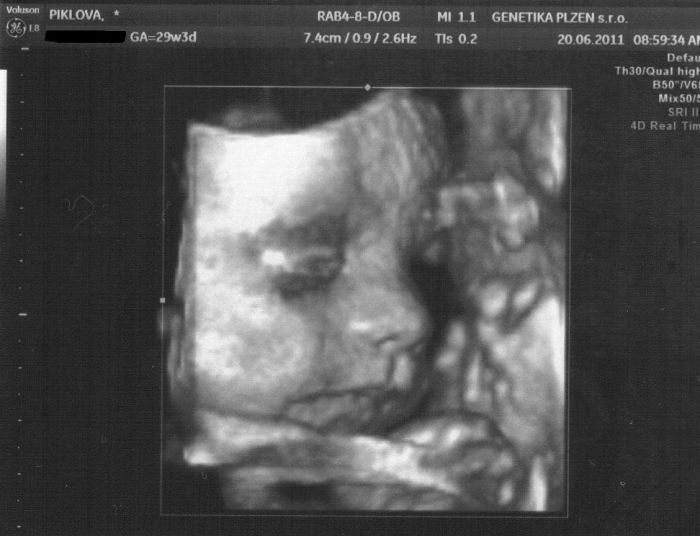

Jinak máš krásnou fotku z 3D. My bohužel máme jen ouško, protože se malá nejdřív nechtěla ukázat a pak před ní bylo málo plodové vody, tak se fotky nepovedly. To mě moc mrzí, ale nenadělám nic.